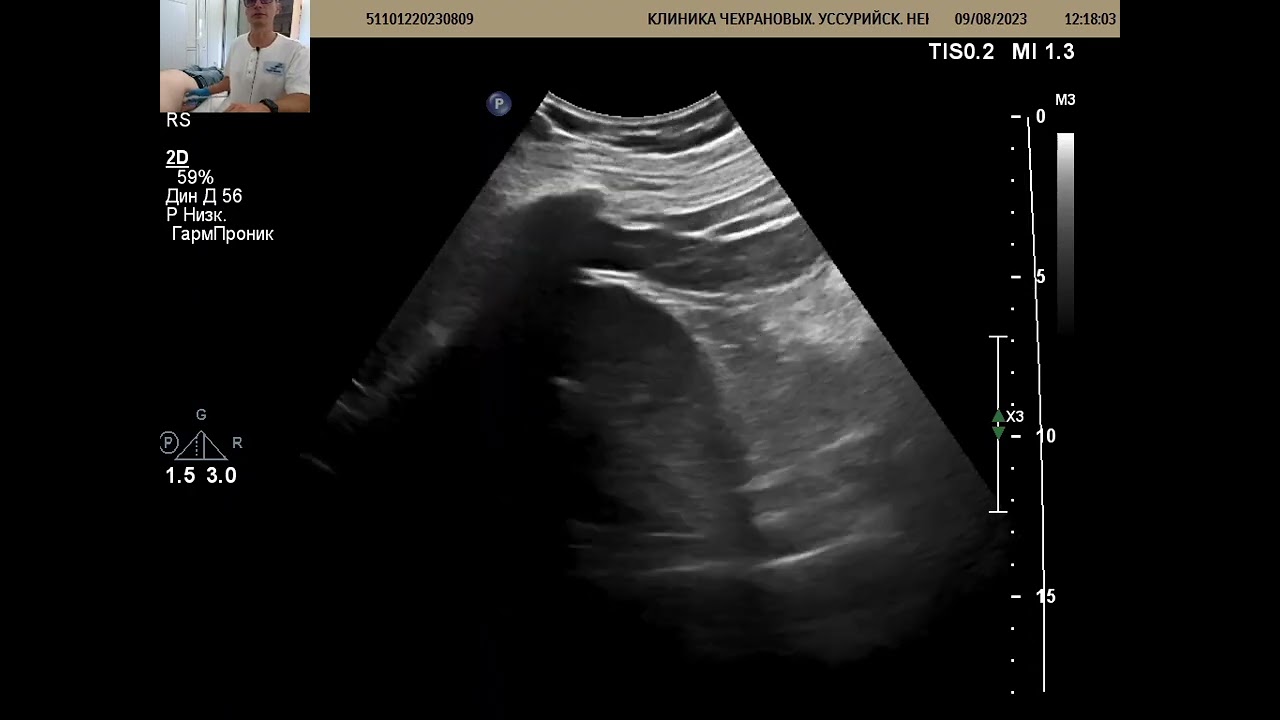

Диагностика при подозрении на уретерогидронефроз состоит из личного осмотра пациента врачом и диагностических методов исследования – лабораторных и инструментальных.

При личном осмотре выясняется анамнез. При пальпации хорошо ощущается увеличенная почка. Больной при этом может ощущать резкую боль внизу живота, которая отдаёт в правое или левое подреберье (в зависимости от локализации и степени поражения органа). После этого, врач назначает инструментальные анализы такого плана:

- УЗИ почек;

Врачи отмечают, что уретерогидронефроз является серьезным состоянием, которое требует внимательного подхода к диагностике и лечению. Это заболевание характеризуется расширением лоханки и чашечек почки, что может быть вызвано различными факторами, включая обструкцию мочевых путей. Специалисты подчеркивают важность раннего выявления проблемы, так как длительное давление на почки может привести к их повреждению и потере функции. Врачи рекомендуют проводить ультразвуковое исследование и другие диагностические процедуры для определения причины обструкции. Лечение может варьироваться от консервативной терапии до хирургического вмешательства, в зависимости от степени тяжести состояния. Профессионалы также акцентируют внимание на необходимости регулярного наблюдения за пациентами, чтобы предотвратить возможные осложнения и сохранить здоровье почек.

Диагностика уретерогидронефроза включает в себя ультразвуковое исследование, компьютерную томографию и анализы мочи. Лечение зависит от причины состояния: в некоторых случаях может потребоваться хирургическое вмешательство для удаления препятствия, в других — консервативные методы, такие как медикаментозная терапия или установка стента для восстановления оттока мочи.